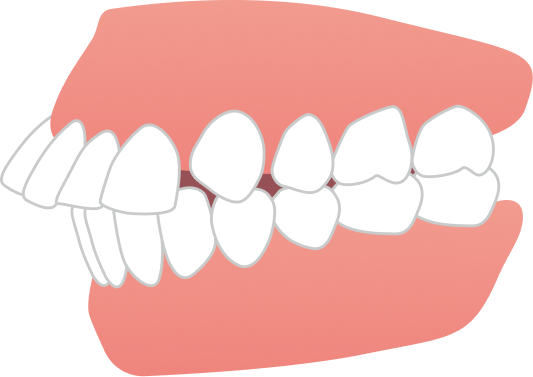

「前歯が出ているのが気になる」「前歯で噛めない」というお悩みでご来院されました。

BEFORE

| 主訴 | 出っ歯、前歯で噛めない(噛み合わせが悪い) |